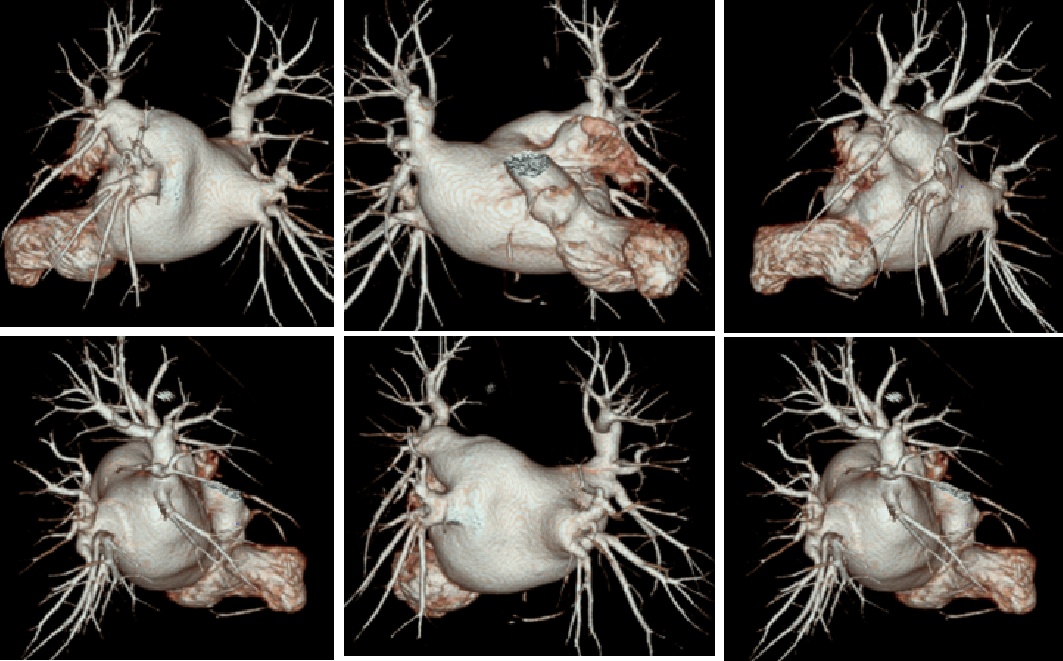

术前左房肺静脉+左心耳CT成像

经食道心脏超声左心耳多角度测量